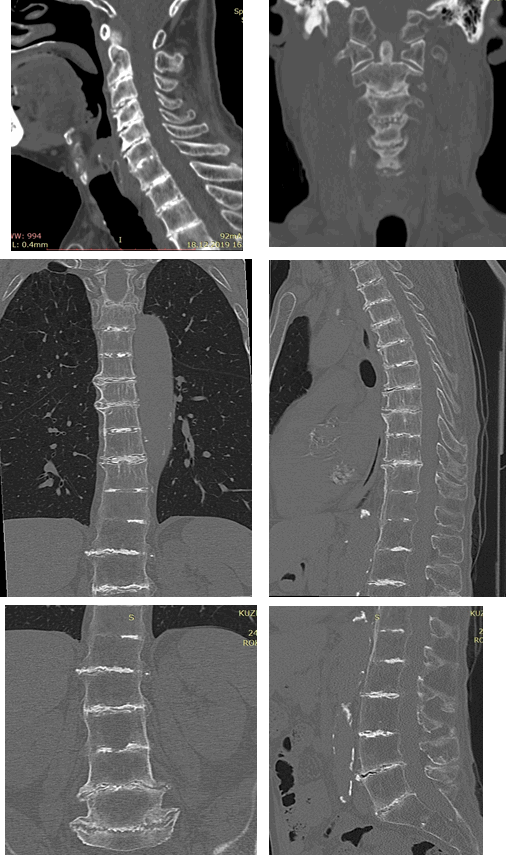

При РКТ шейного, грудного и поясничного отделов позвоночника определялась сглаженность физиологических изгибов позвоночника, резкое снижение высоты межпозвонковых дисков на всех уровнях, кальцификация дисков, выраженные дегенеративные изменения всех замыкательных пластинок в виде остеосклероза и неровностей контуров, краевые остеофиты и синдесмофиты; частичный анкилоз сегментов С6-С7, Th11-Th12, Th12-L1, выраженные дегенеративные изменения в дугоотростчатых суставах, обызвествление передней продольной связки, грудо-поясничный сколиоз, диффузный остеопороз. КТ-картина соответствовала охронозу (рис. 5).

Рис. 5. На компьютерных томограммах шейного, грудного и поясничного отделов позвоночника пациента Н. определяются распространенные дегенеративные изменения, обызвествление межпозвонковых дисков, сколиоз, диффузный остеопороз, склерозирование и окостенение боковых и передней связок позвоночника

Таким образом, лучевая картина при исследовании пациента, страдающего охронозом, оказалась весьма демонстративной. Имели место характерные изменения в шейном, грудном и поясничном отделах позвоночника: на фоне остеопороза тел позвонков выраженные уплотнения студенистого ядра и фиброзного кольца, а также боковых отделов позвонка, в силу чего последний напоминал рамку для фотографий («рамочный позвонок») при рентгенографии. Высота межпозвонковых дисков резко снижена, имела место оссификация боковых и передней связок позвоночного столба. Также отмечались выраженные вторичные остеоартрозные изменения в плечевых и коленных суставах (субхондральный остеосклероз, разрушение хряща в виде сужения рентгеновских суставных щелей, неровность суставных поверхностей, краевые костные разрастания), что, по данным литературы, является довольно частым и типичным явлением при охронозе.